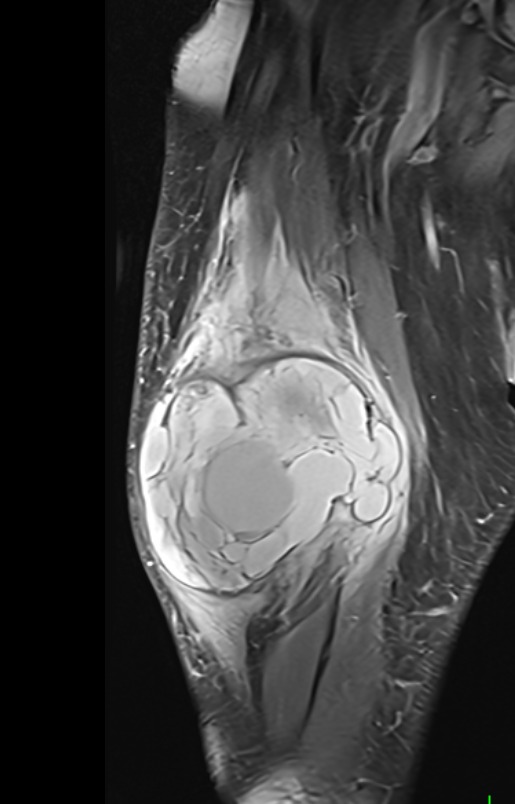

Muscle Cancer